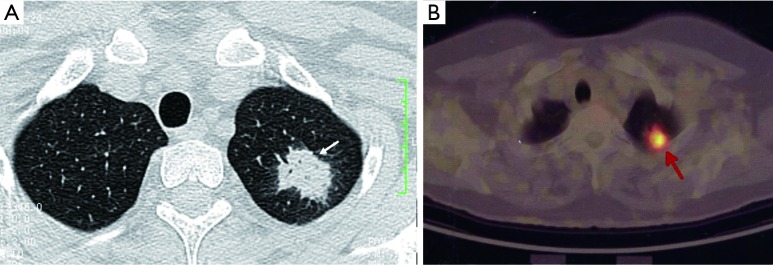

Figure 12.

PET-CT shows a case of atypical adenomatous hyperplasia with a SUVmax of 1.42.

In most studies, the sensitivity of 18F-FDG PET-CT tends to be higher than its specificity for assessment of SPN. Many benign conditions, such as granulomatous (for example histoplasmosis or tuberculosis) and inflammatory processes, can mimic malignant nodules and produce false-positive results (Figure 13) (86). On the other hand, false negative results for SPN characterization on PET-CT can occur in three main settings: small lesion size, low tumor metabolic activity, and hyperglycemia. Small lesions (<1 cm) are challenging due to limited spatial resolution of PET, which is approximately 7 mm for modern scanners (7). Some highly differentiated malignant tumors have relatively little metabolic activity and low rate of proliferation, resulting in false-negative PET-CT. FDG PET is falsely negative in around 50% of patients with bronchioloalveolar carcinoma (87), or adenocarcinoma in situ (88-90). In addition, metastasis from certain primary malignancy, such as renal cell carcinoma, testicular or prostate cancer, may show little FDG tracer accumulation and may even be undetectable on PET-CT (91). False negative FDG PET-CT scans may also occur in patients with hyperglycemia (77). Some authors have proposed dual time point FDG-PET imaging, using the change in SUVmax between early and delayed scans to help differentiate benign and malignant SPNs (92). However, the role of dual time point PET imaging (DTPI) has been disputed by some authors (93). A meta-analysis on diagnostic performance of dual time point FDG-PET imaging in assessing lung nodules reported similar sensitivity and specificity to single time point FDG-PET (94). Further studies are needed to clarify this point.

Figure 13.

A case of cryptococcal granuloma (arrow) had a SUVmax of 4.5 on the FDG PET scan.